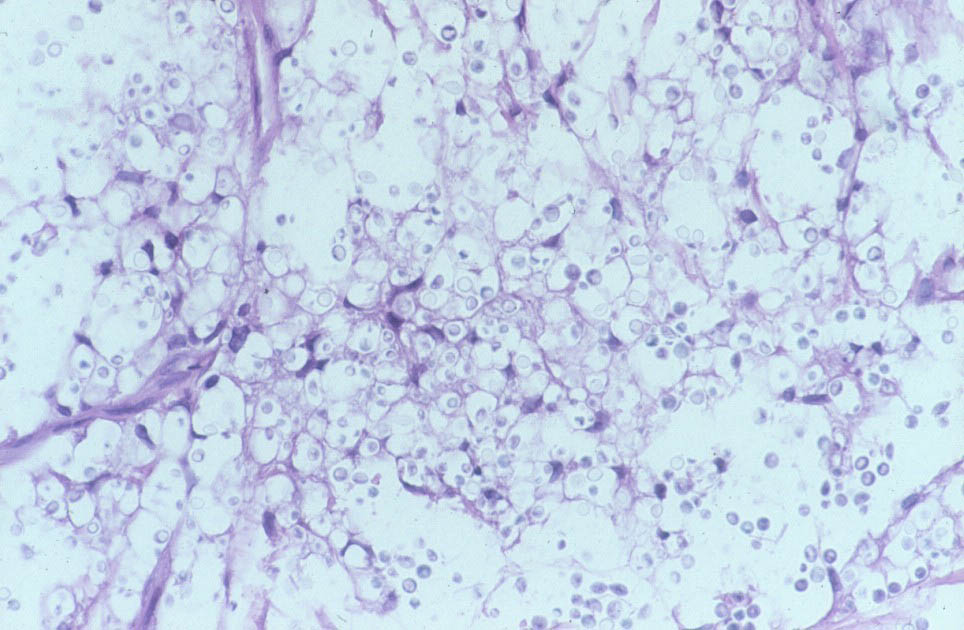

Histologic FindingsIn spinal fluid, urine, and tissue, pathogenic strains of C neoformans grow as round-to-oval yeast, surrounded by a polysaccharide capsule composed of mannose, xylose, and glucuronic acid. The yeast may be single or may have a single budding daughter cell. Cell size varies widely and ranges from 3.5-8 µm in diameter. Rarely, pseudohyphae develop.

India ink, which outlines the organisms by negative contrast, helps to identify the yeast cells in fluids or macerated tissue samples. In fixed tissue, the capsule of C neoformans may also be stained with mucicarmine, which preferentially stains mucopolysaccharides. Tissue sections can be stained with the Fontana-Masson stain to detect melanin precursors in the yeast cell wall. The presence of melanin or melanin precursors is useful in differentiating C neoformans from other yeasts. |